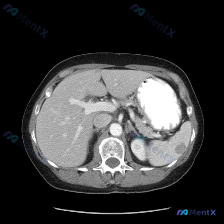

这次的腹部CT平扫,重点异常在脾脏:

- 脾脏实质内可见数个类圆形低密度影,边界相对清晰

- 病灶密度均匀,低于周围正常脾实质

- 肝脏、胰腺、胃腔、腹主动脉等其余腹部主要结构,在扫描层面内未见明确异常